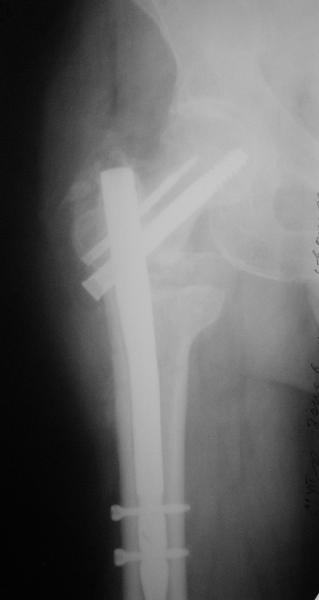

Дистракция позволит улучшить шеечно-диафизарный угол. Фиксировать технически проще пластиной, оптимально 130-градусной. Можно и с другим углом, только спланируйте тщательно, как должен быть направлен шеечный элемент, чтобы не оставить варус.

Гвоздем тоже можно, но технически труднее, надо вводить джойстики в шейку...

В приложении пример с гвоздем.